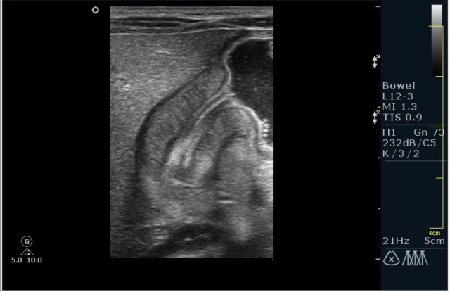

Ребёнок 1 месяц 10 дней от родy, с отсуствием прибавки в весе.

Hypertrophic pyloric stenosis.

Criteria:

1.Pyloric channel > 12 mm in length

2.Muscular layer thickness > 3-4 mm

3.Donuts sign at transverse scanning

Признак "пончика".

А что, похоже.